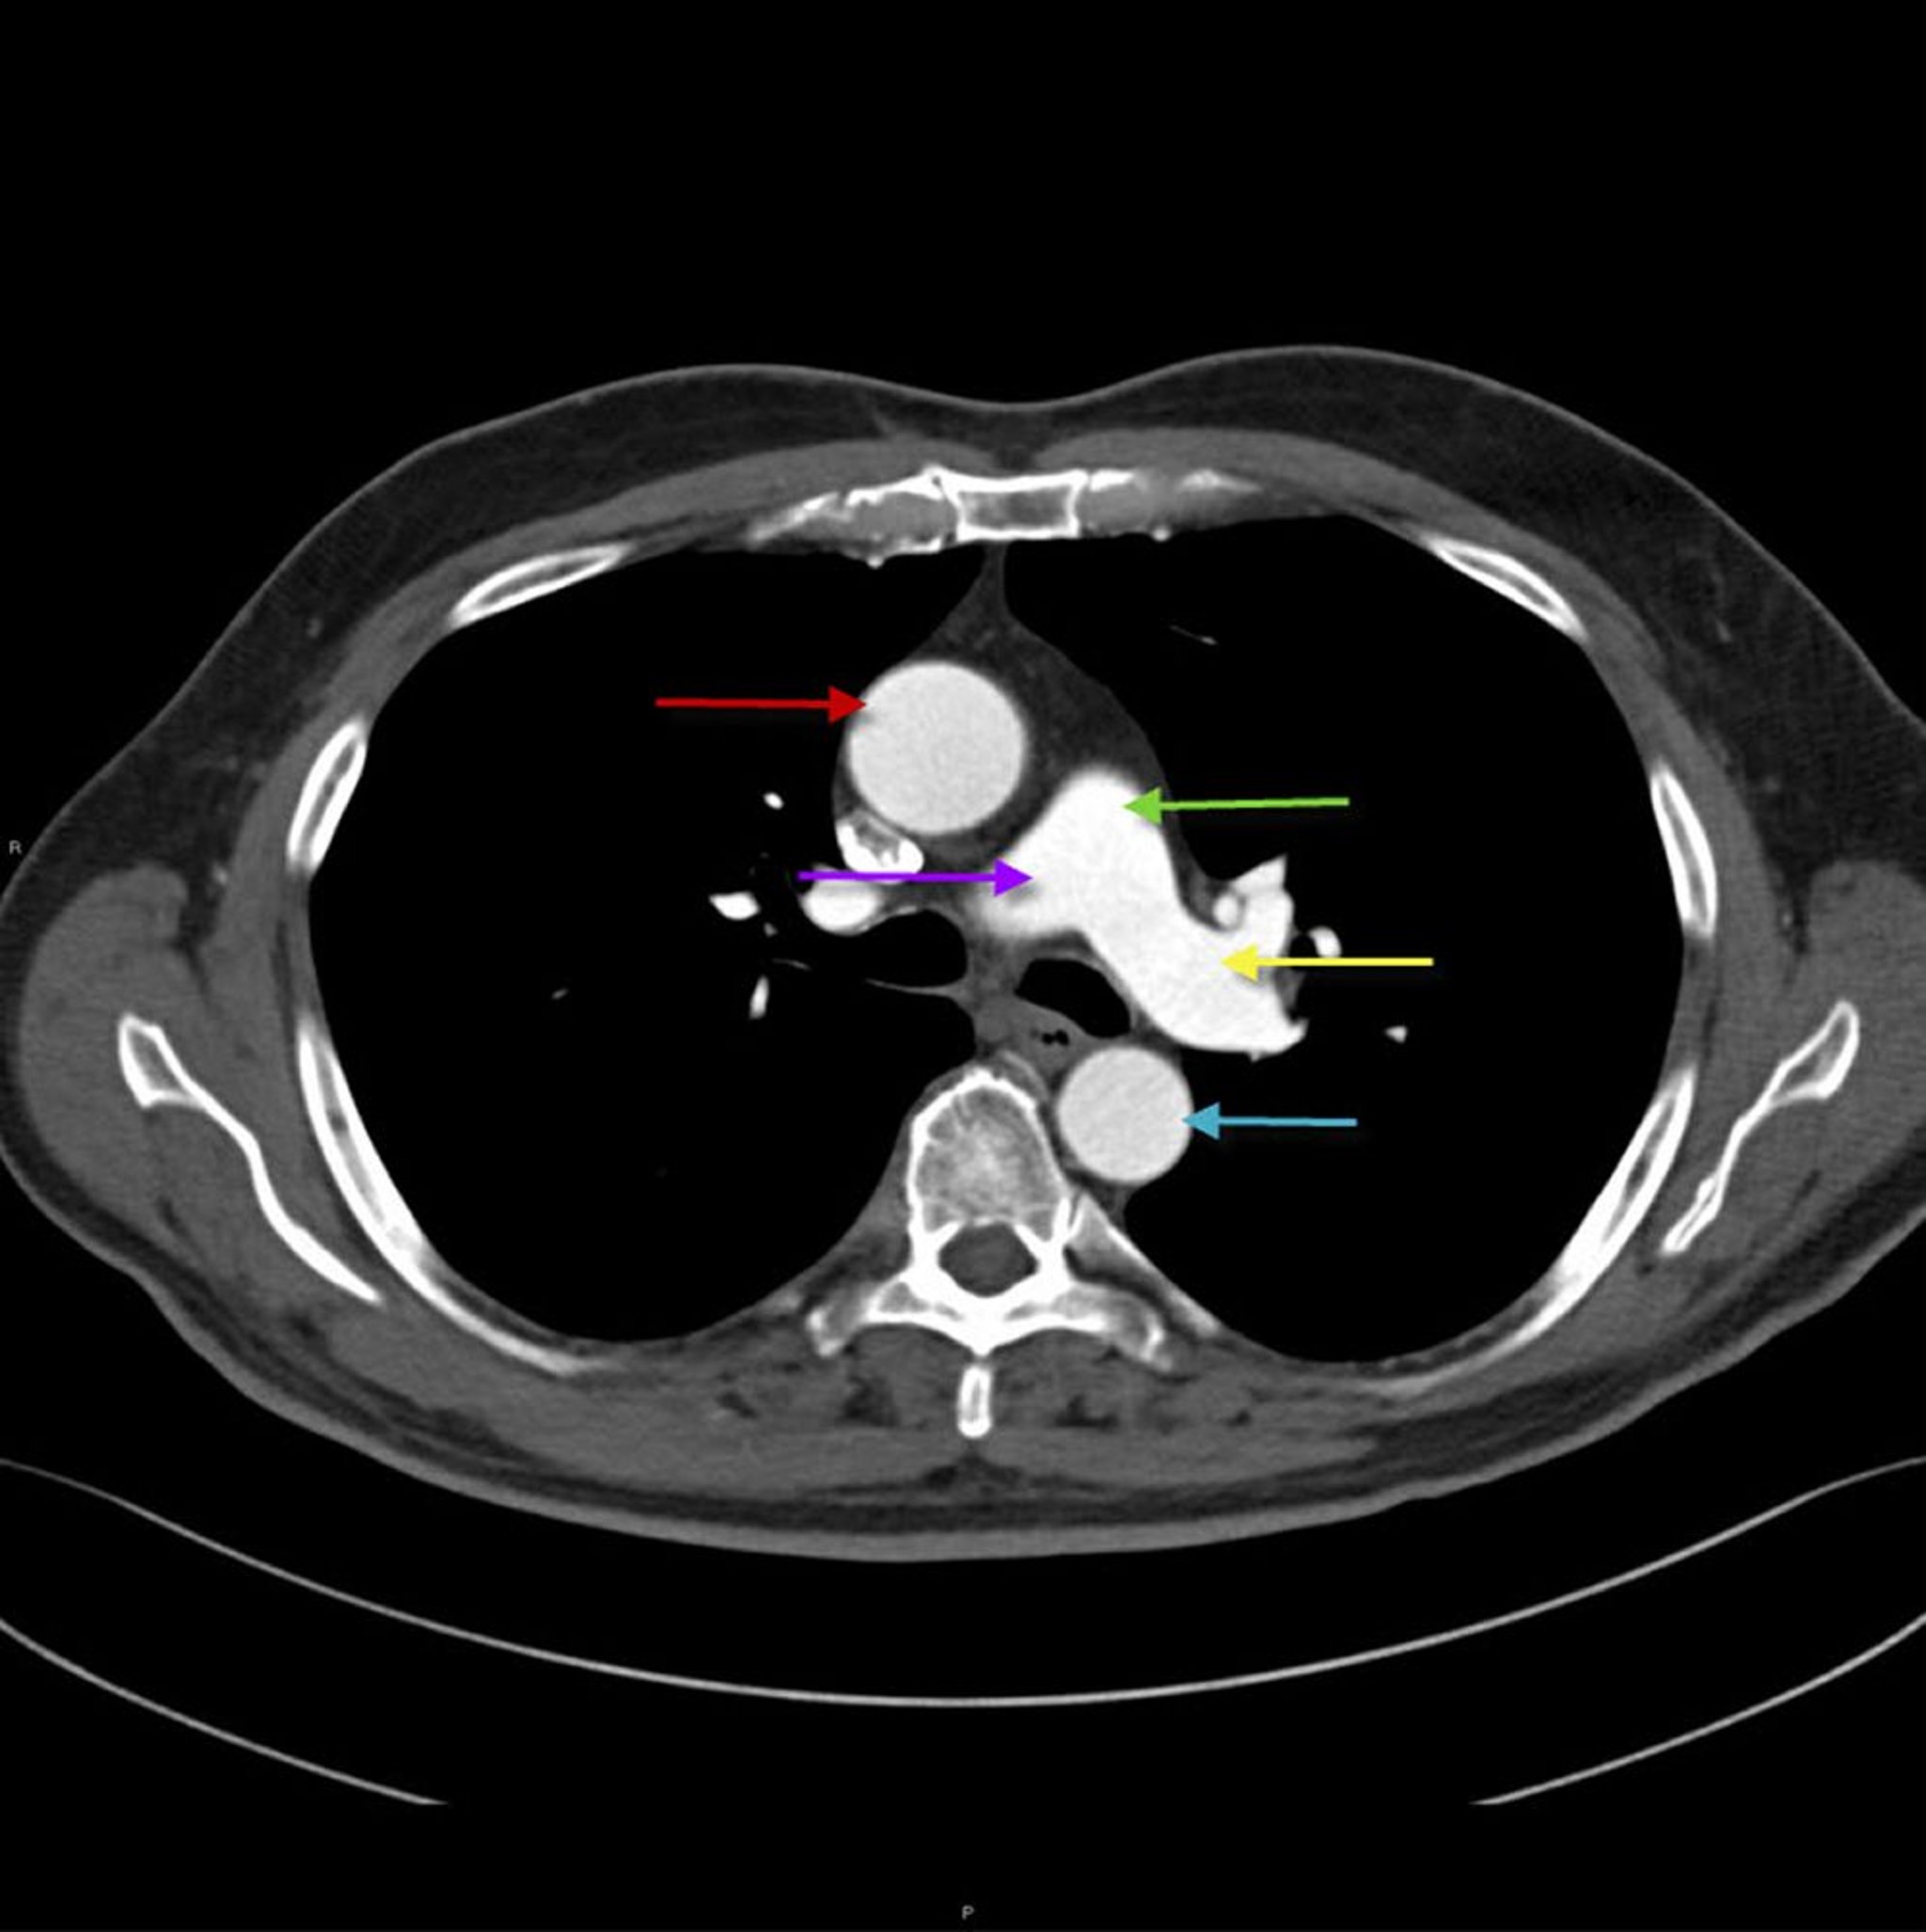

TC del torace che mostra l'anatomia dell'aorta e dell'arteria polmonare

Questa immagine mostra l'aorta toracica ascendente (freccia rossa) con l'aorta toracica discendente (freccia blu). L'arteria polmonare principale (freccia verde) si divide nell'arteria polmonare destra (freccia viola) e sinistra (freccia gialla).